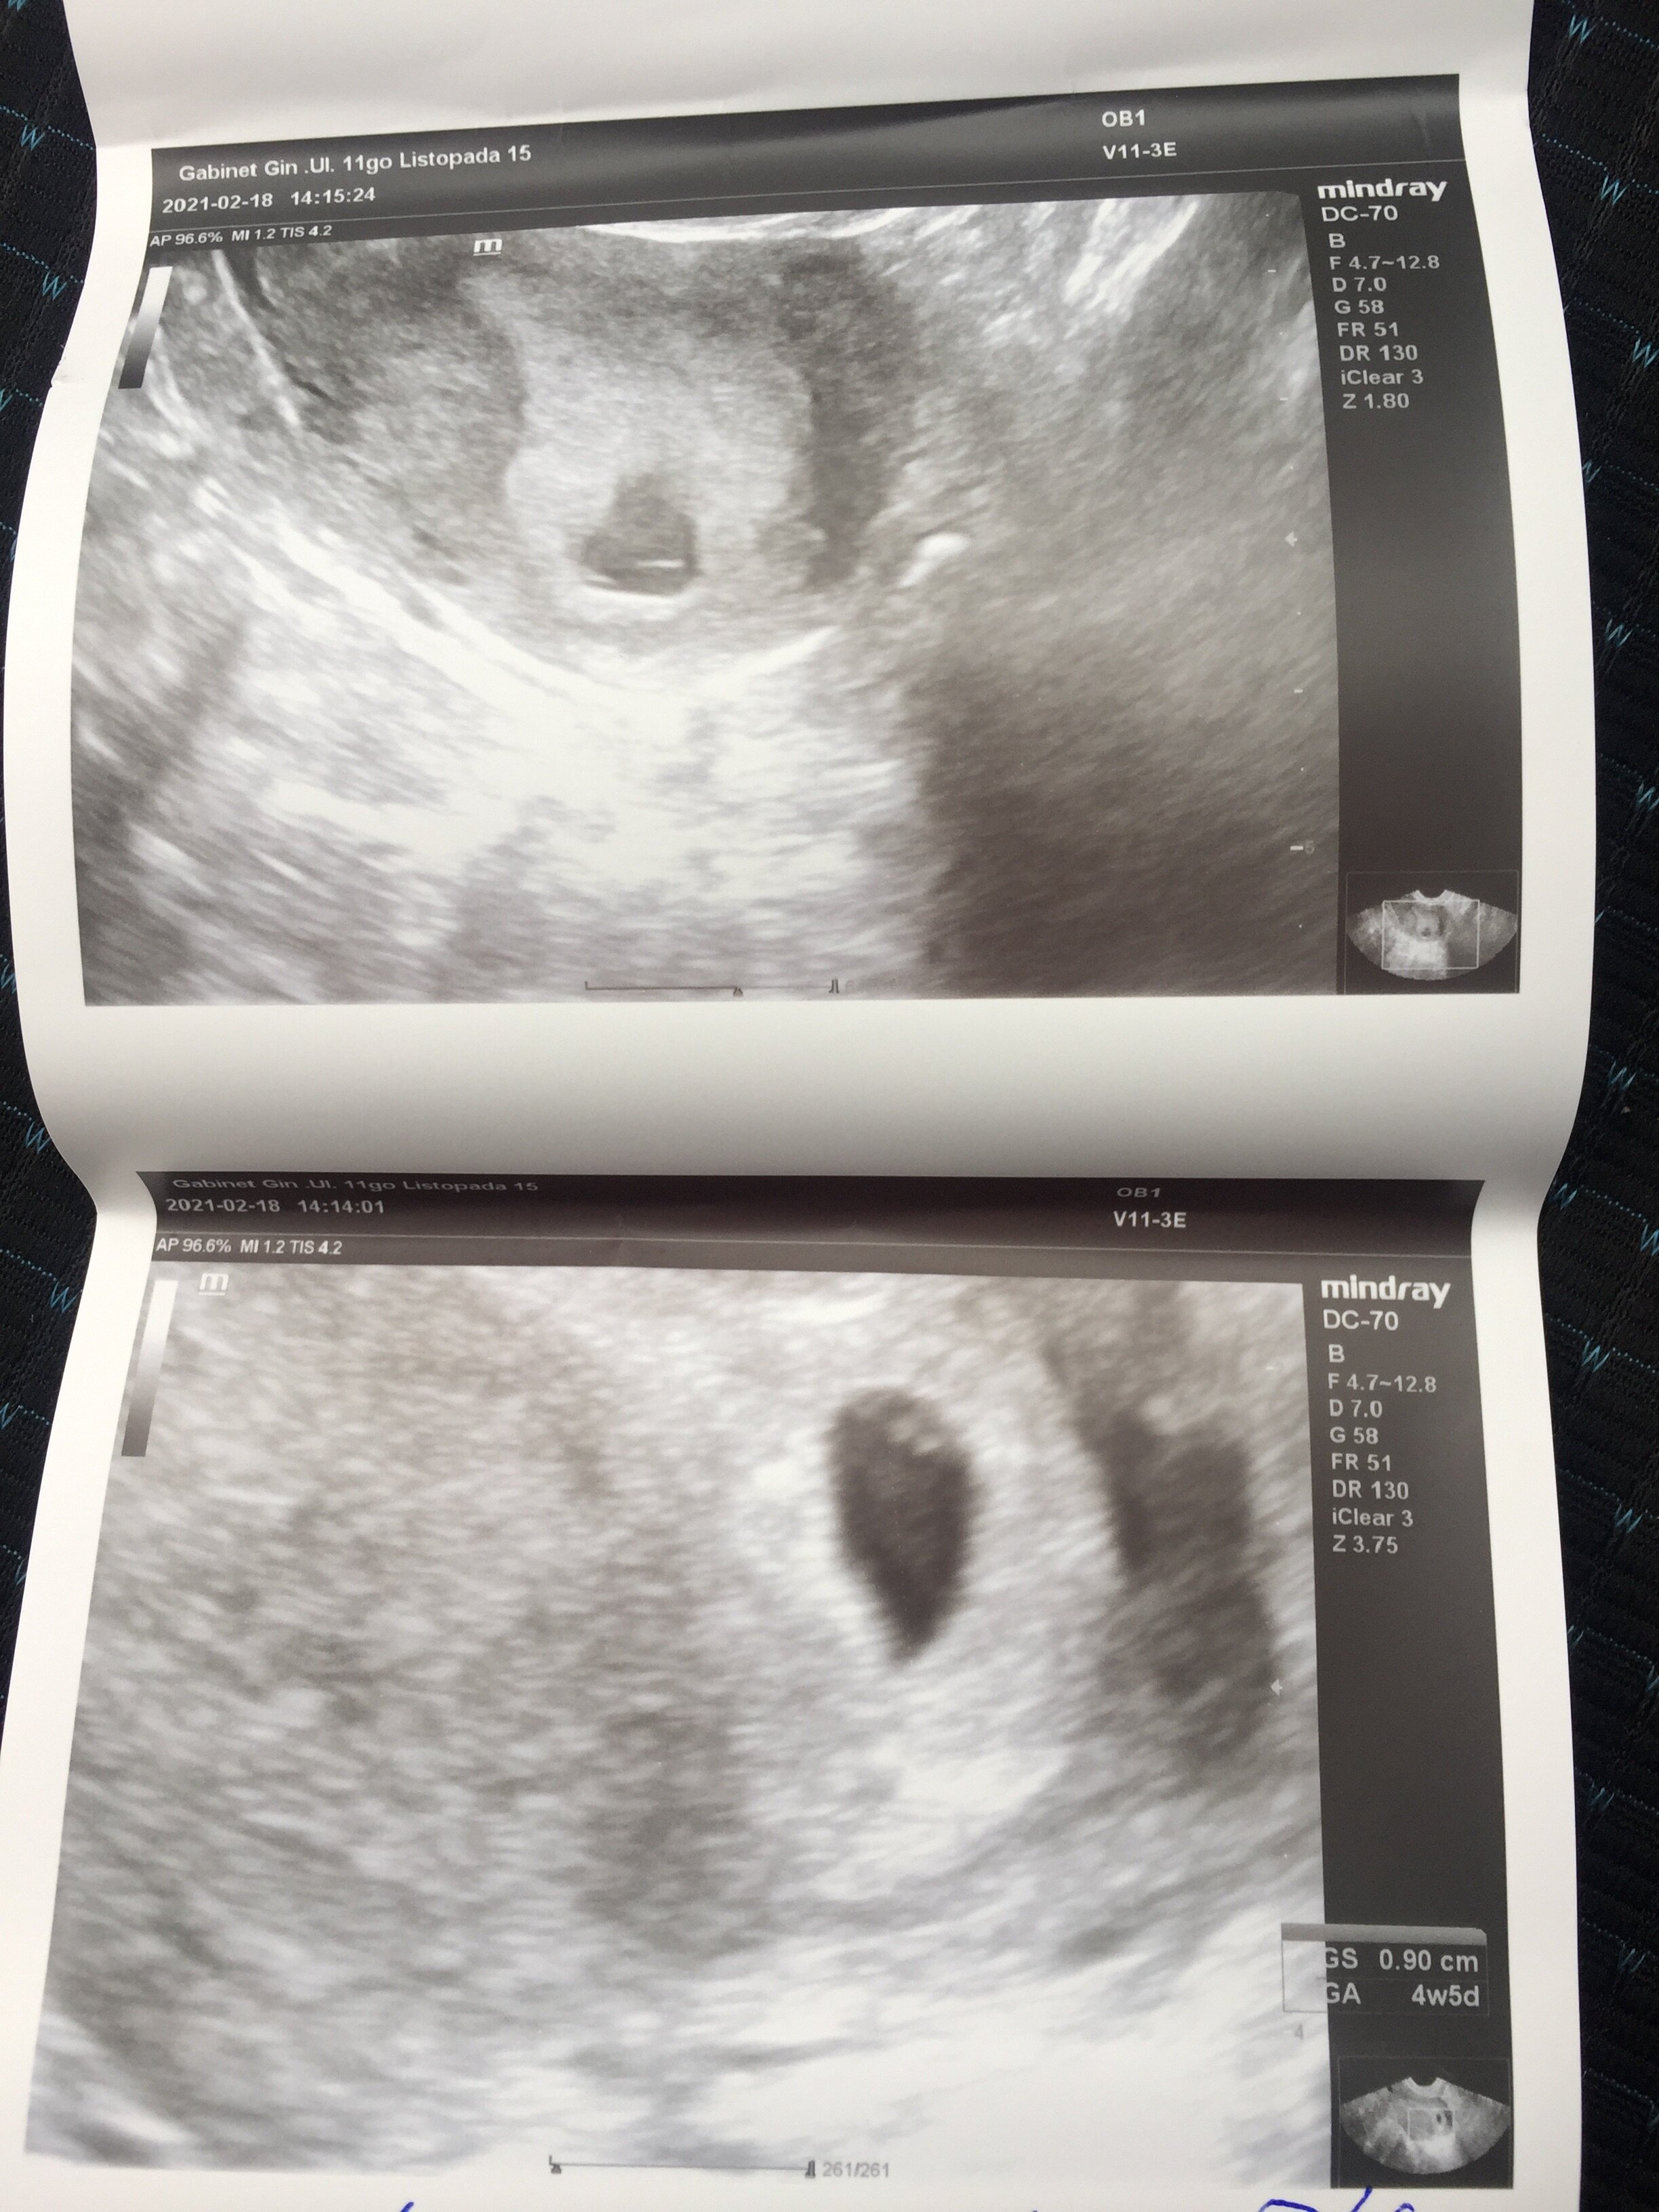

Zobacz załącznik 1239734Ja już po wizycie, zarodek umiejscowiony w macicy, ma niecałe 1cm. Ale nie wiem czy widzicie różnice miedzy zdjęciami. Albo to poniżej to krwiaczek, albo drugi zarodek 😳 jestem przerażona! Dziś wyszło z usg 4+5 kolejna wizyta za 2 tyg no i dostałam Dupasthon 2x1